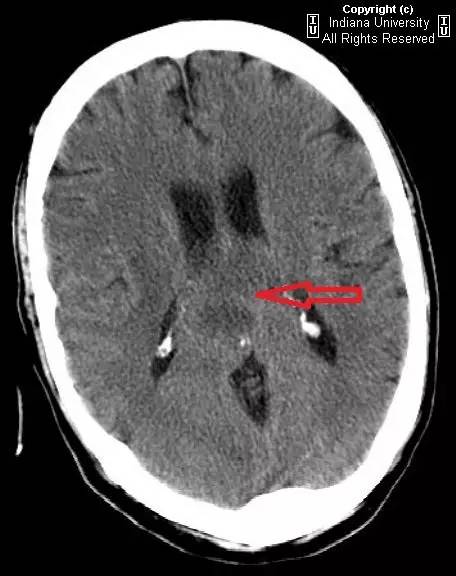

图 1 平扫 CT,病变累及胼胝体压部(红色箭头),密度不均,向两侧扩展,压迫双侧脑室

可见一中心位于胼胝体压部的占位性病变,密度不均,中心为低密度,周围环状水肿。推压双侧脑室。右侧侧脑室室管膜极有可能受累。占位蔓延进入双侧半卵圆中心,右侧明显。MR 上,病灶成周边强化,中央无强化低信号表明有坏死性改变。